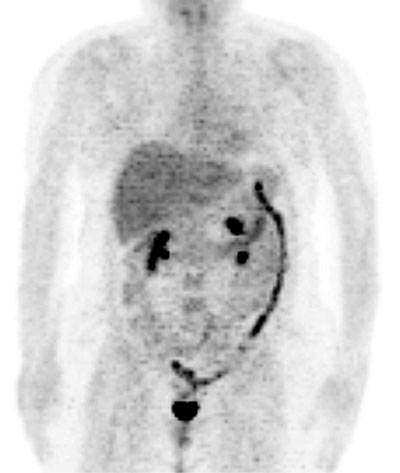

| Fig. 14. - Imágenes coronal de tomografía por emisión de positrones de cuerpo completo. Mujer de 46 años operada de cáncer de mama derecha con posterior tratamiento quimioterápico. En PET de control se aprecia persistencia de la enfermedad en área esternal, así como aumento fisiológico de captación de la [18]FDG en colon (desde colon transverso a recto). |